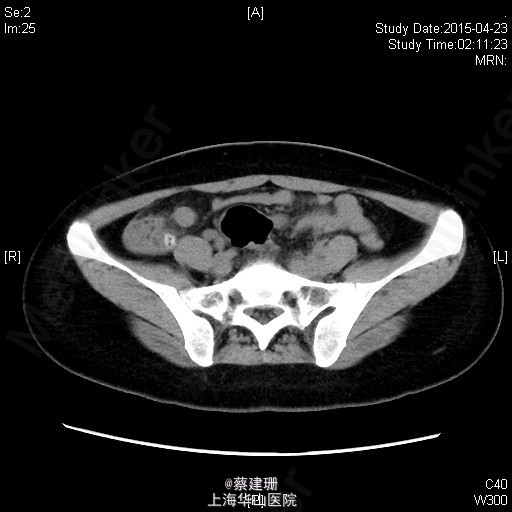

急性阑尾炎(粪石?)伴局限性腹膜炎

患者 女性 24岁,因“转移性右下腹痛一天余。”入院。患者一天前无明显诱因下出现中上腹疼痛,无恶心呕吐,无腹泻。10小时前疼痛转移至右下腹,原先中上腹疼痛缓解,无发热无腹泻。患者未予重视,后疼痛难忍于今日凌晨至我院急诊就诊,血常规示:WBC:18.63*10^9/L,我院B超示:右下腹见肠段局限性扩张,炎性病灶待排。肝胆胰脾肾未见明显异常,双输尿管未见扩张。我院CT示:阑尾增大壁增厚内见高密度影及低密度气体影,符合阑尾炎改变,盆腔少量积液。患者拒绝行急诊手术,故予以保守治疗,患者症状未缓解,右下腹疼痛加重。为行进一步诊治,收入院。

全身皮肤粘膜未见异常,无肝掌,全身浅表淋巴结无肿大。腹平坦,腹壁软,右下腹压痛,伴有肌紧张及反跳痛,麦氏点压痛(+),肝脾肋下未触及,肝肾脏无叩击痛,肠鸣音4次/分。 辅助检查:血常规示:WBC:18.63*10^9/L,N:89%。我院B超示:右下腹见肠段局限性扩张,炎性病灶待排。肝胆胰脾肾未见明显异常,双输尿管未见扩张。我院CT示:阑尾增大壁增厚内见高密度影及低密度气体影,符合阑尾炎改变,盆腔少量积液。

入院后诊断:急性阑尾炎伴局限性腹膜炎。完善相关检查,全麻下行腹腔镜下阑尾切除术。术后恢复可,伤口无明显渗出,予以出院。